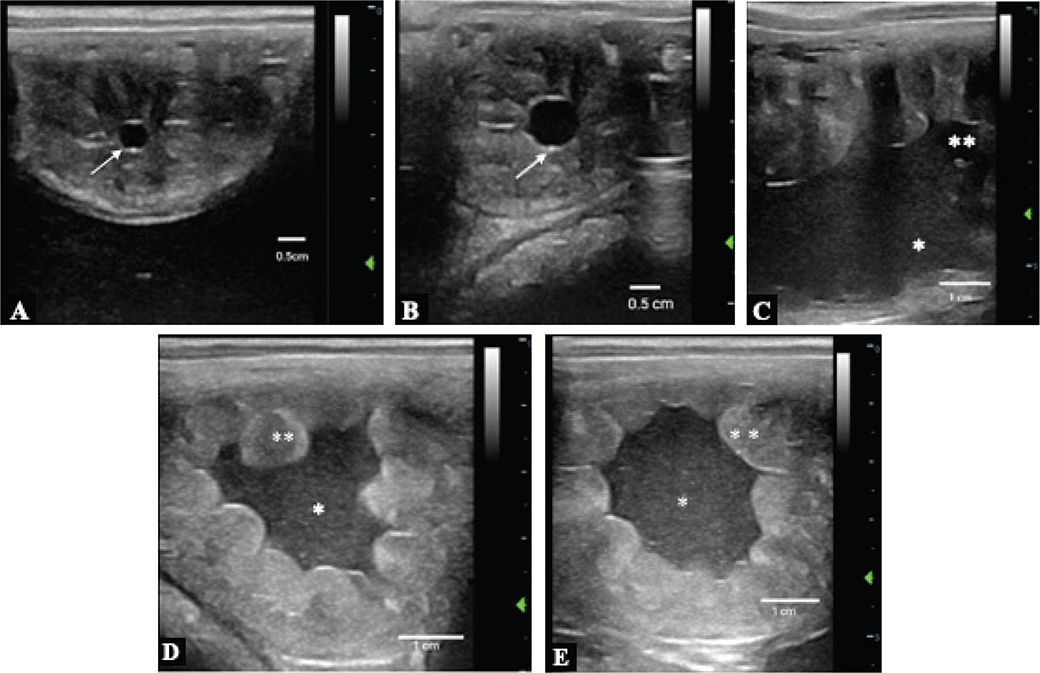

Figure 1.

Figure 1. Transrectal ultrasonographic images of uterus: A. Day 10 embryonic vesicle (white arrow) of 0.4 cm and grade 1 endometrial edema; B. Day 11 embryonic vesicle (white arrow) of 0.8 cm and grade 2 endometrial edema; C. Day 12 embryonic vesicle; D and E. Days 13 and 14 embryonic vesicle (note hyperechoic free fluid visible in the uterine lumen* and uterine mucosa edema**)

On day 10, transrectal ultrasonography revealed an embryonic vesicle along with slight endometrial edema (Figure 1A). The next day, the vesicle had increased in size (Figure 1B), but on day 12, the vesicle was no longer visible in transrectal ultrasonography. Instead, a considerable amount of hyperechoic intrauterine fluid was present (Figures 1C-E). On day 14, endometrial culture (with antibiogram) and cytology (cytobrush) were collected. The endometrial cytology was negative (0% polymorphonuclear neutrophils [PMN]) but the endometrial culture resulted in moderate growth of S. zooepidemicus (result made available on day 16). Progesterone concentrations had dropped considerably from day 11 to day 12. Detailed description of clinical and laboratory findings is provided (Table). Based on these findings, an acute endometrial bacterial endometritis followed by premature luteolysis and early embryonic death were diagnosed.

Although embryonic vesicle size was within the physiological range indicating normal conceptus development on days 10 and 11,28 growth had ceased on day 12 demonstrating a switch to abnormal embryo development often indicative of early pregnancy loss.29 At this period, also progesterone concentrations had considerably dropped which paralleled by increasing endometrial edema indicating return of the mare to estrus.30 In addition, the sudden appearance of free intrauterine fluid suggested an endometrial inflammatory condition.